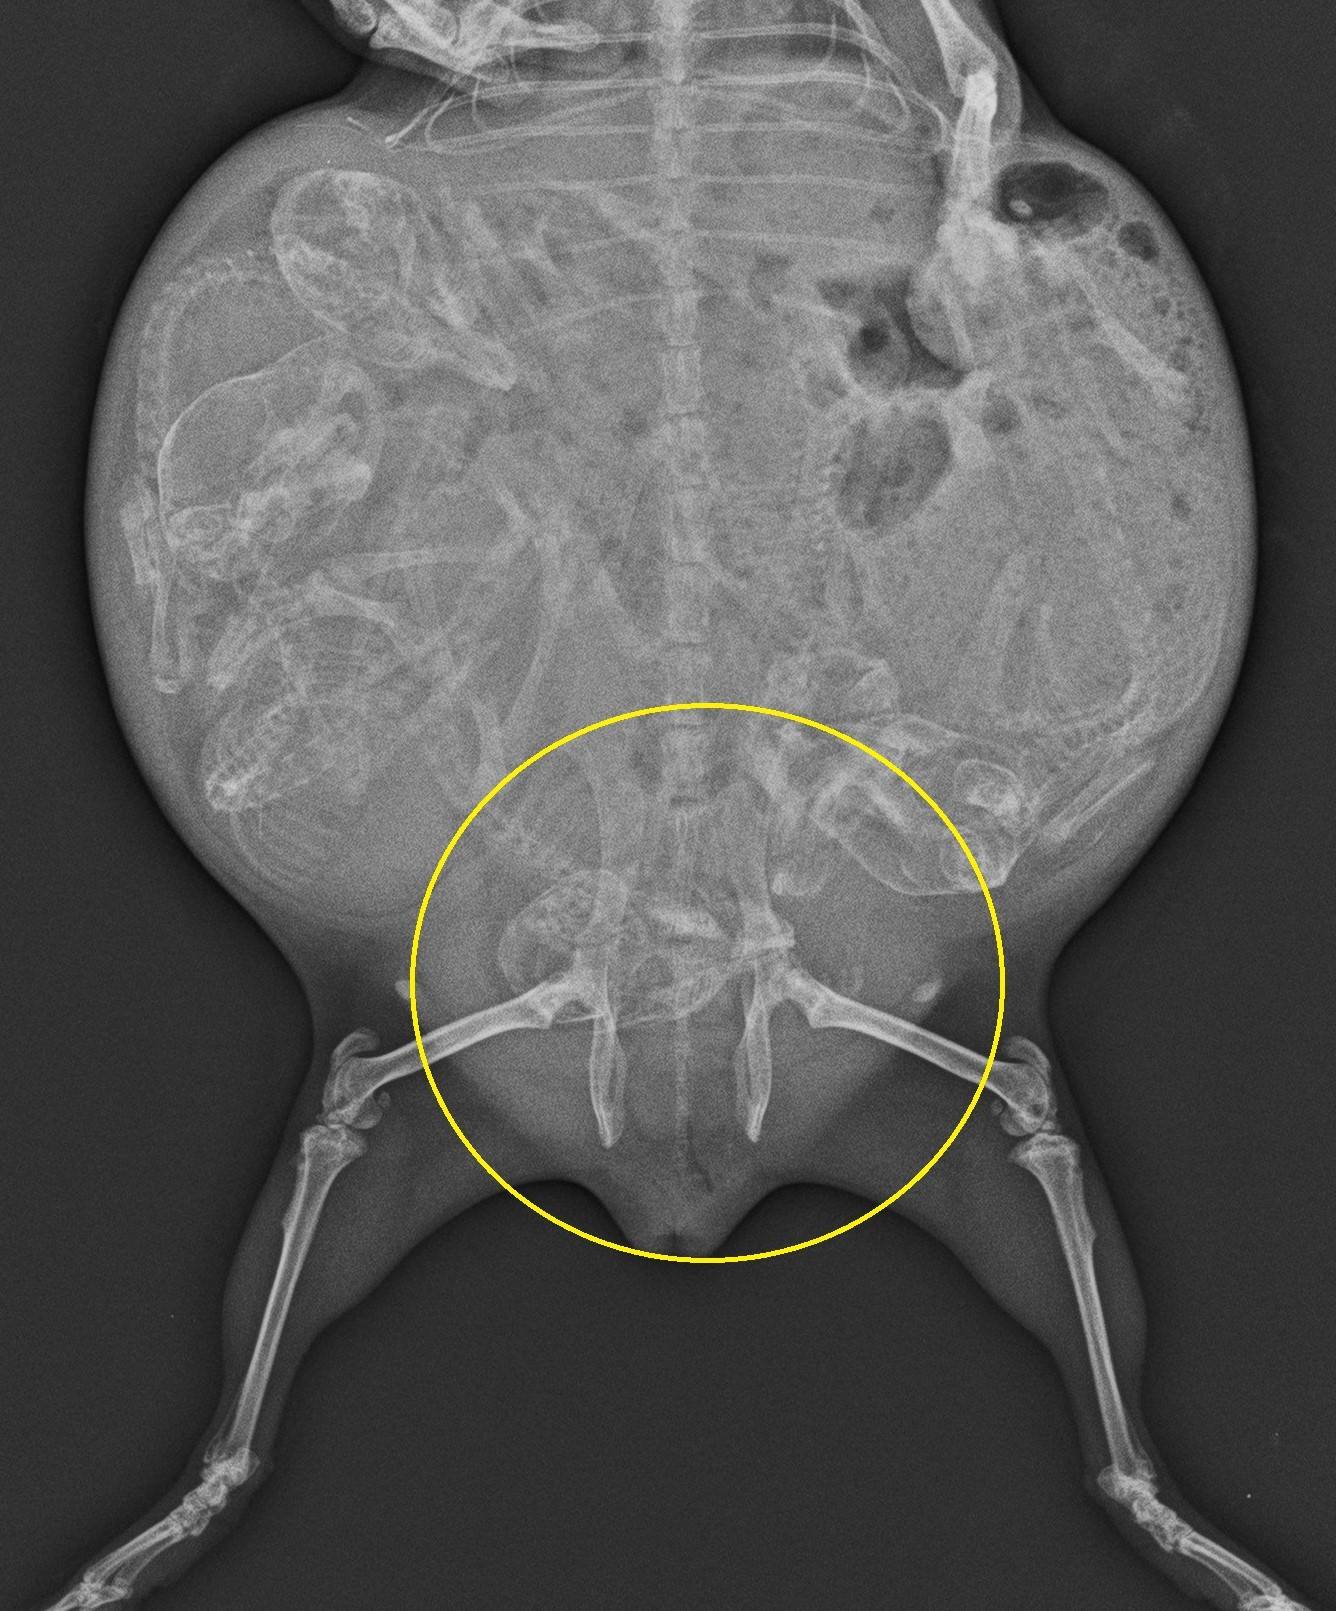

もう一度レントゲン撮影をしました。

お母さんの様子に変化はありません。

赤ちゃんが成長しすぎてしまうと難産になってしまうこともあります。

赤ちゃんの大きさ、恥骨結合の開き、お母さんモルの様子から

十分に出産の準備はできていると判断し、出産を促すホルモン剤を投与することにしました。